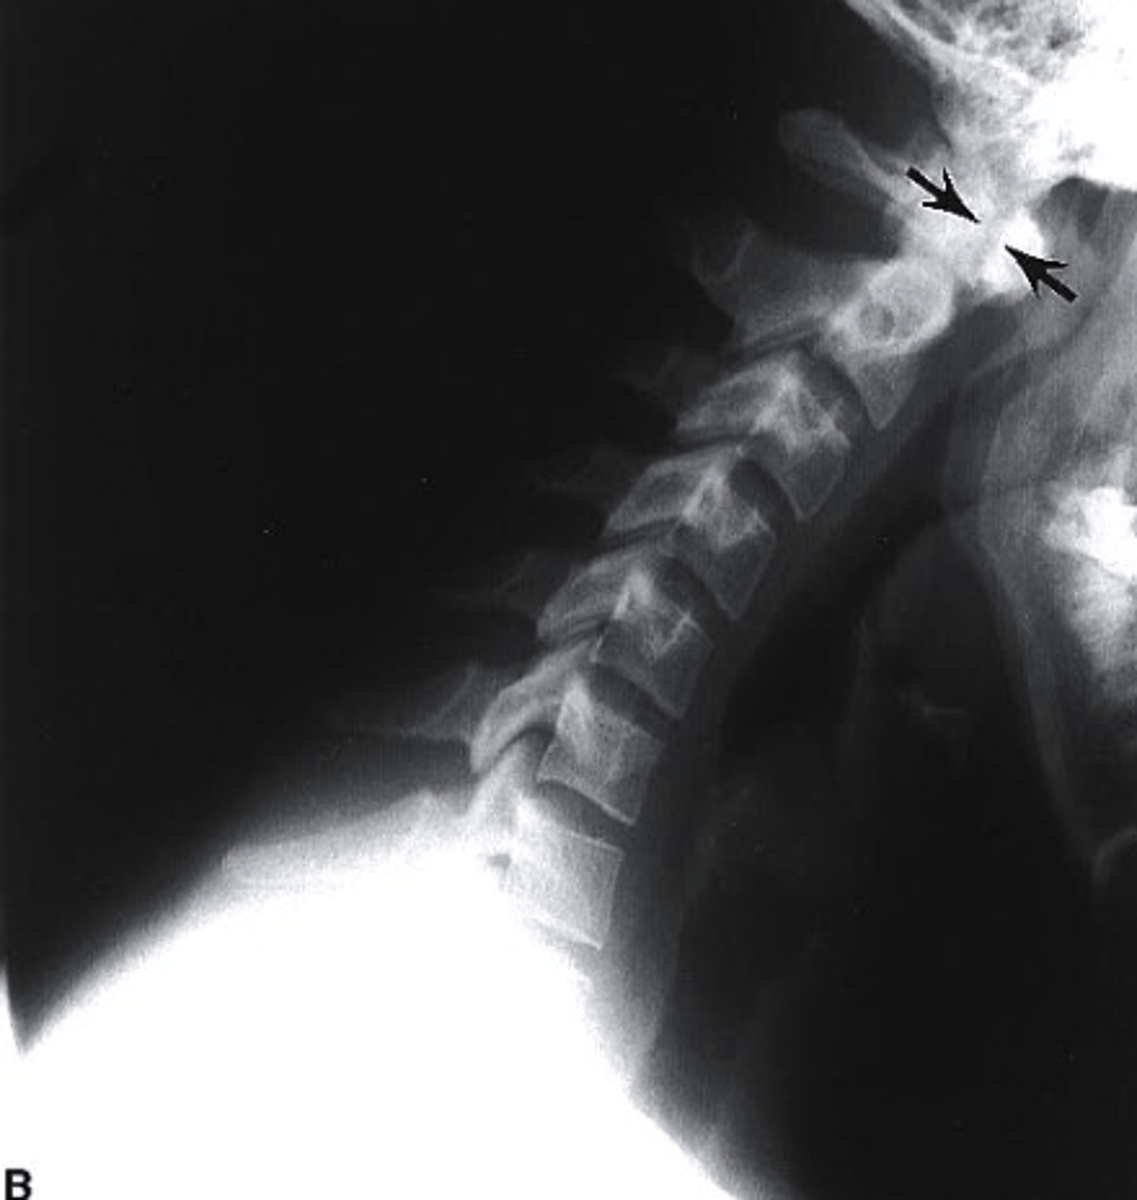

extension stress

what view is this?

a. extension stress

b. flexion stress

c. lateral

d. oblique

flexion stress